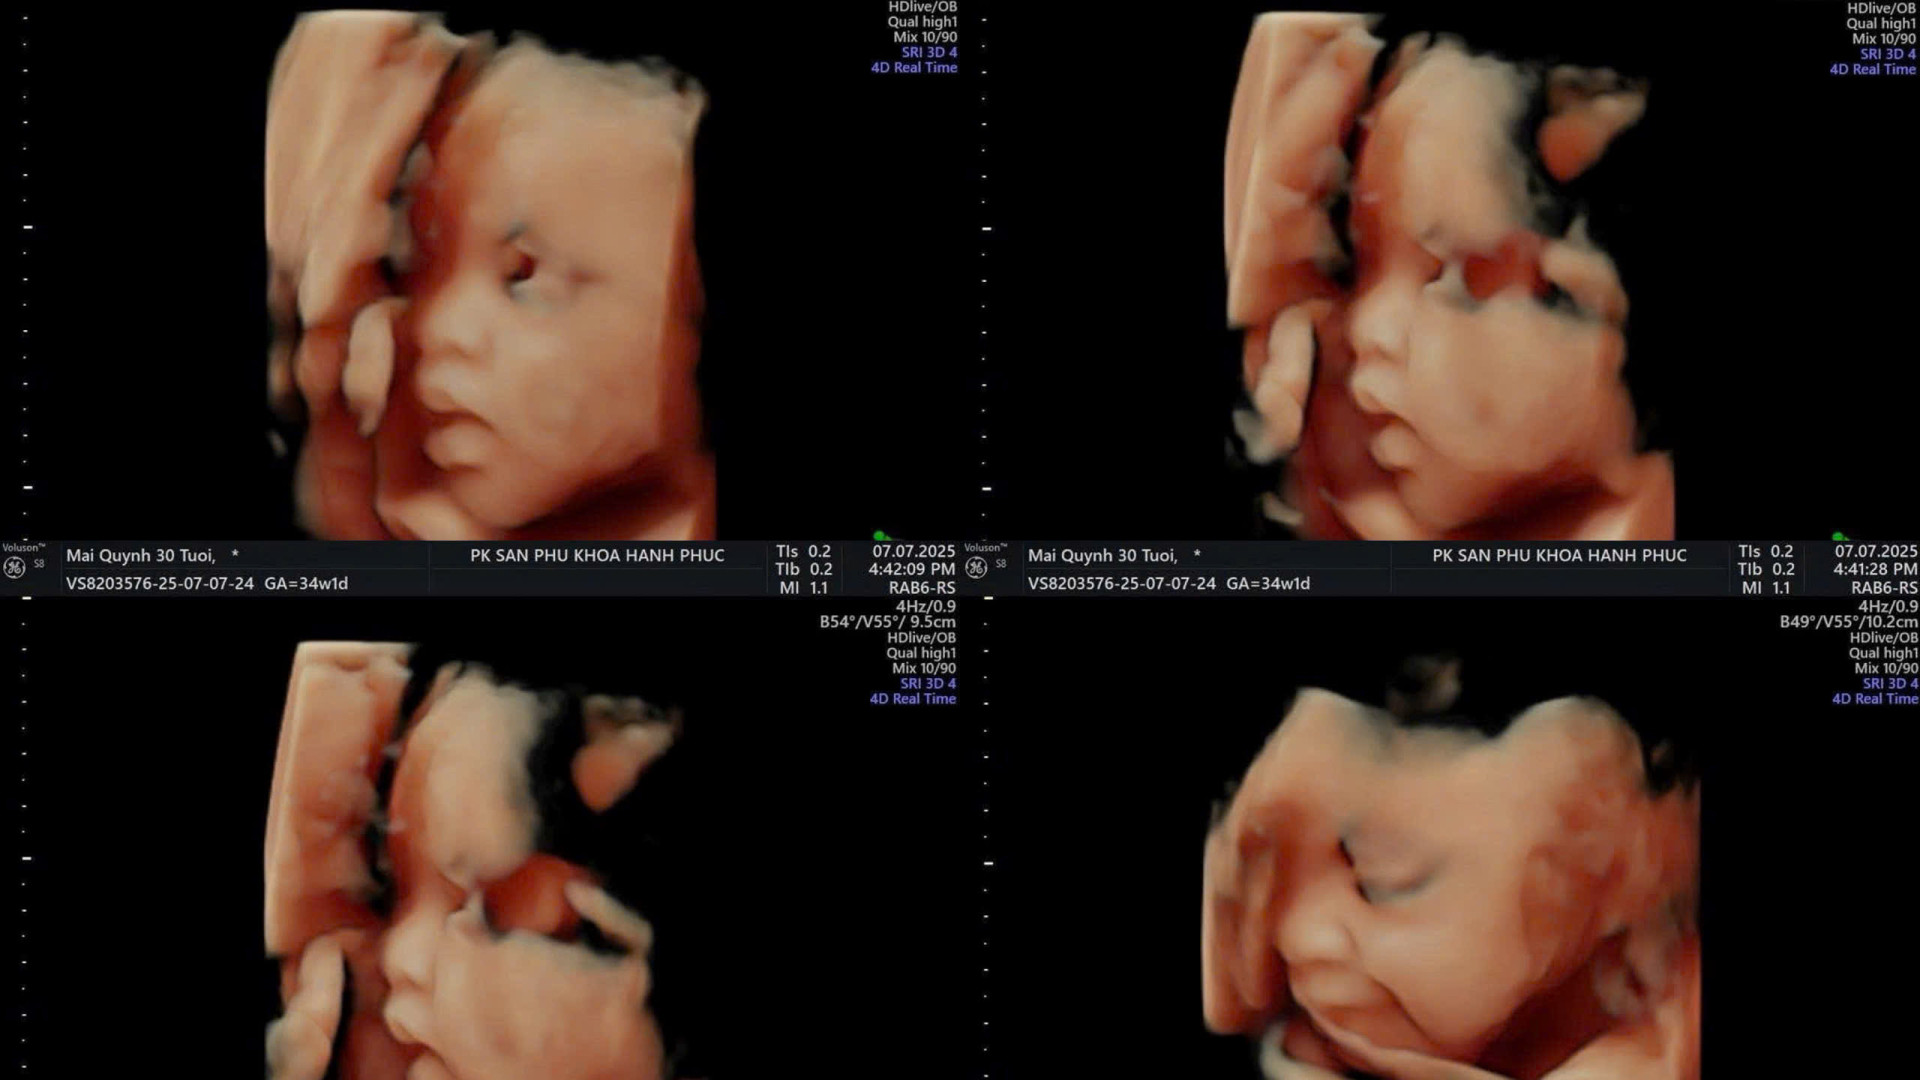

Hiện tại, diễn viên Quỳnh Lương đang ở tháng thứ 8 của thai kỳ. Kể từ khi công bố mang thai lần 2, người đẹp khá cởi mở khi chia sẻ những câu chuyện xoay quanh cuộc sống mẹ bầu.

"Bị nhỏ 2,4kg tác động vật lý chật vật không ngủ được. Đau xương sườn, thượng vị, đau hai bên lưng, đau xương cụt, đau xương chậu, đau vết mổ cũ. Em cần báo chính quyền", Quỳnh Lương cho biết.